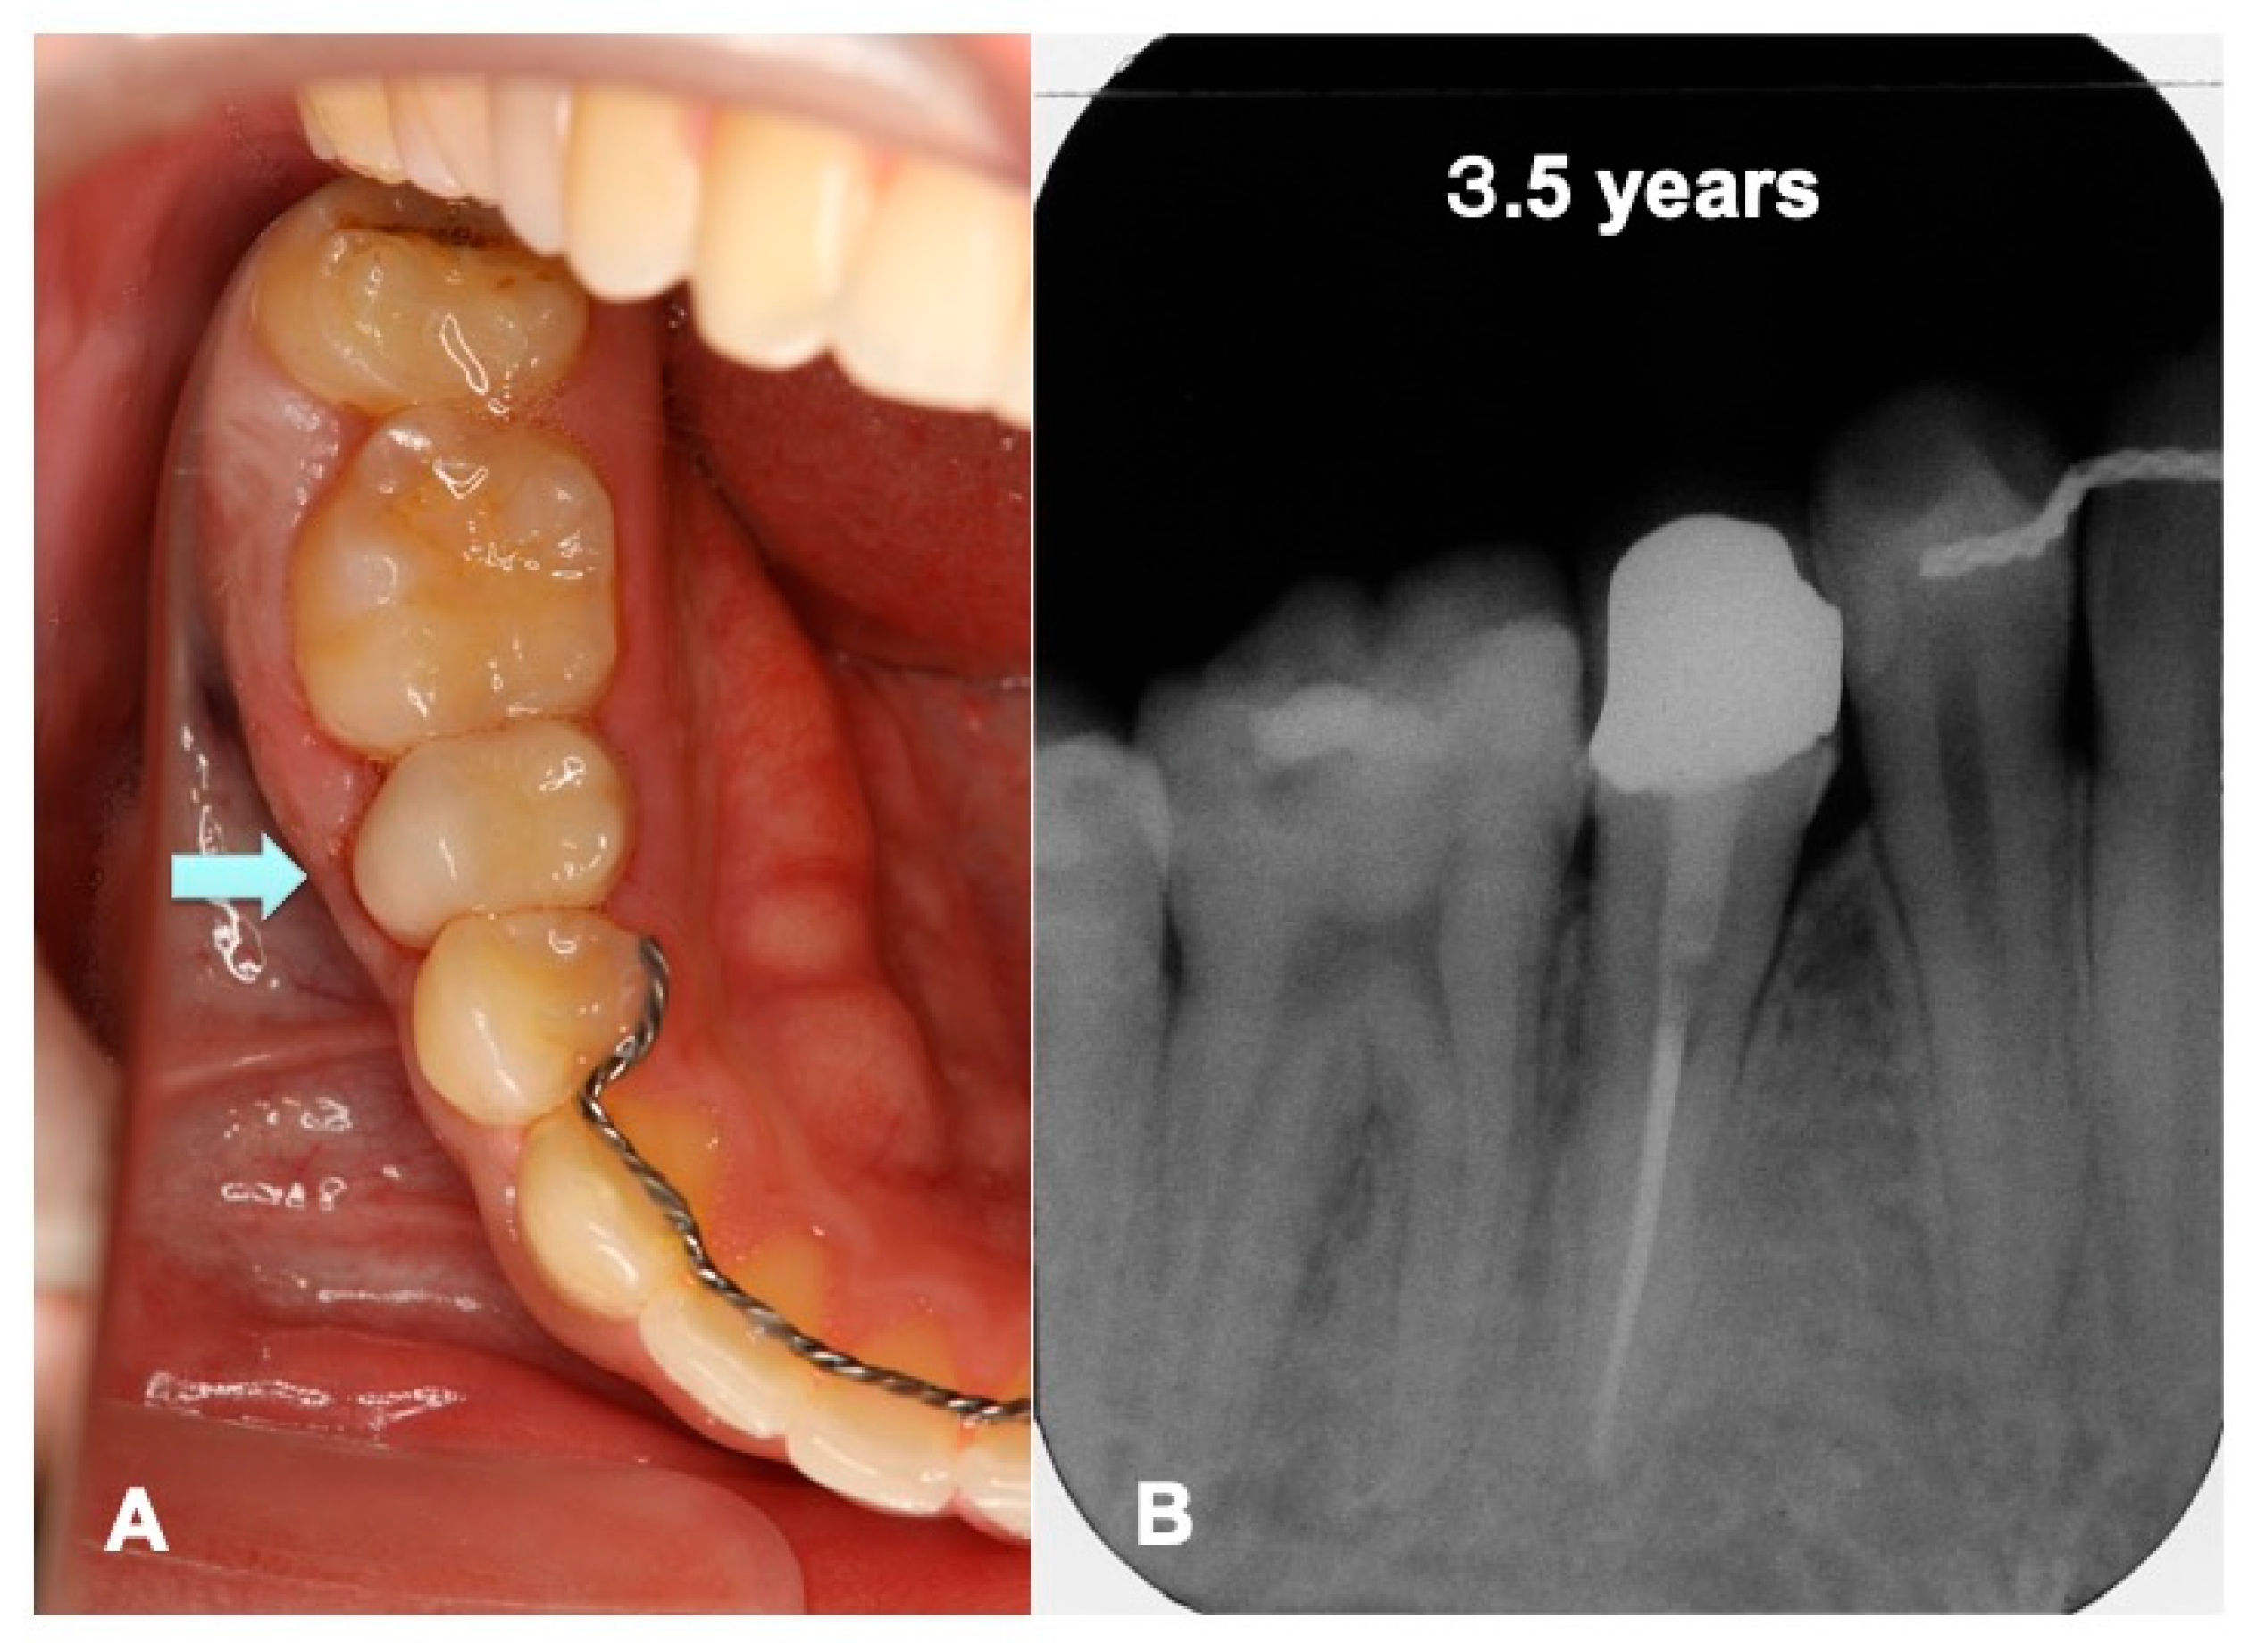

3. Results

3.1. Gross View and Examinations after Surgery

3.2. Radiographic Evaluation